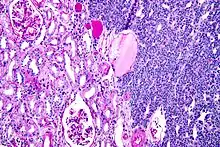

| Micrograph of a metanephric adenoma with structures reminiscent of those seen in papillary renal cell carcinoma. H&E stain. | |

Metanephric adenoma is diagnosed histologically. The tumours can be located at upper pole, lower pole and mid-hilar region of the kidney; they are well circumscribed but unencapsulated, tan pink, with possible cystic and hemorrhagic foci. They show a uniform architecture of closely packed acinar or tubular structures of mature and bland appearance with scanty interposed stroma.[3][4][5][6][7] Cells are small with dark staining nuclei and inconspicuous nucleoli. Blastema is absent whereas calcospherites may be present. Glomeruloid figures are a striking finding, reminiscent of early fetal metenephric tissue. The lumen of the acini may contain otherwise epithelial infoldings or fibrillary material but it is quite often empty. Mitoses are conspicuously absent.[3][4][5][6][7] In the series reported by Jones et al. tumour cells were reactive for Leu7 in 3 cases of 5, to vimentine in 4 of 6, to cytocheratin in 2 of 6, to epithelial membrane antigen in 1 of 6 cases and muscle specific antigen in 1 of 6.[8] Olgac et al. found that intense and diffuse immunoreactivity for alpha-methylacyl-CoA racemase (AMACR) is useful in differentiating renal cell carcinoma from MA but a panel including AMACR, CK7 and CD57 is better in this differential diagnosis.[9] Differential diagnosis may be quite difficult indeed as exemplified by the three malignancies initially diagnosed as MA that later metastasized, in the report by Pins et al.[10]